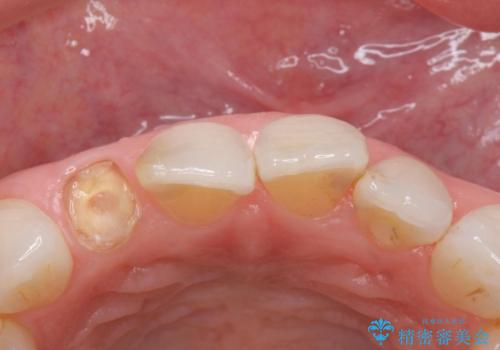

- 右上の前歯が取れたとのことで来院された患者様です。

再根管治療からのやり直しをご提案しましたが、ご希望されなかったため土台(コア)のやりかえからとなりました。

- 右上2 仮歯/11,000円 ファイバーコア/22,000円 ジルコニアクラウン(スペシャル)/154,000円 合計187,000円費用は治療当時の料金となります